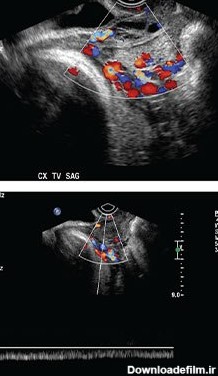

عکس رنگی رحم یا هیستروسالپنگوگرافی یکی از روش های تشخیصی شیوه ی تصویربرداری با اشعه ایکس است که معمولاً برای بررسی آناتومی رحم و لوله ها انجام میشود. عکس رحم

نمونه برداری از مایع آمنیوسنتز یا مایع دور جنین کرج 09192955748میثم موسوی راد کارشناس رادیولوژیهیستروسونوگرافی و هیستروگرافی یا عکس رنگی رحم یا (HSG) با بی حسی